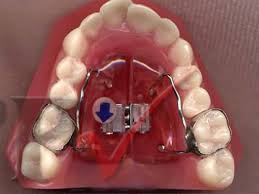

Disjuntor mais utilizado em disjunções rápidas da maxila. O HYRAX é um aparelho expansor preso aos dentes pela parte interna junto ao céu da boca. Quanto ao hyrax espero também não ter que ativa-lo mais.

Aparelho dentário adicione um dos valores acima conforme o aparelho escolhido. Ambos são construídos com o uso de fios muito rígidos e soldados ao parafuso disjuntor palatino. 71 reais con 35 centavos R 71.

Ele é usado em casos que o osso maxilar é muito estreito.

Ambos são construídos com o uso de fios muito rígidos e soldados ao parafuso disjuntor palatino. Quanto custa um expansor Palatino. E quais as indicações. Hyax com menor preço e entrega rápida. Já para o fixo estético brackets transparentes o preço deve variar entre R 100000 a R 250000. Mas de modo geral os valores que podem ser aplicados são estes. O aparelho de Haas é suportado pelos dentes e também pela mucosa do palato do paciente. Aparelho no céu da boca. 35 10 OFF.